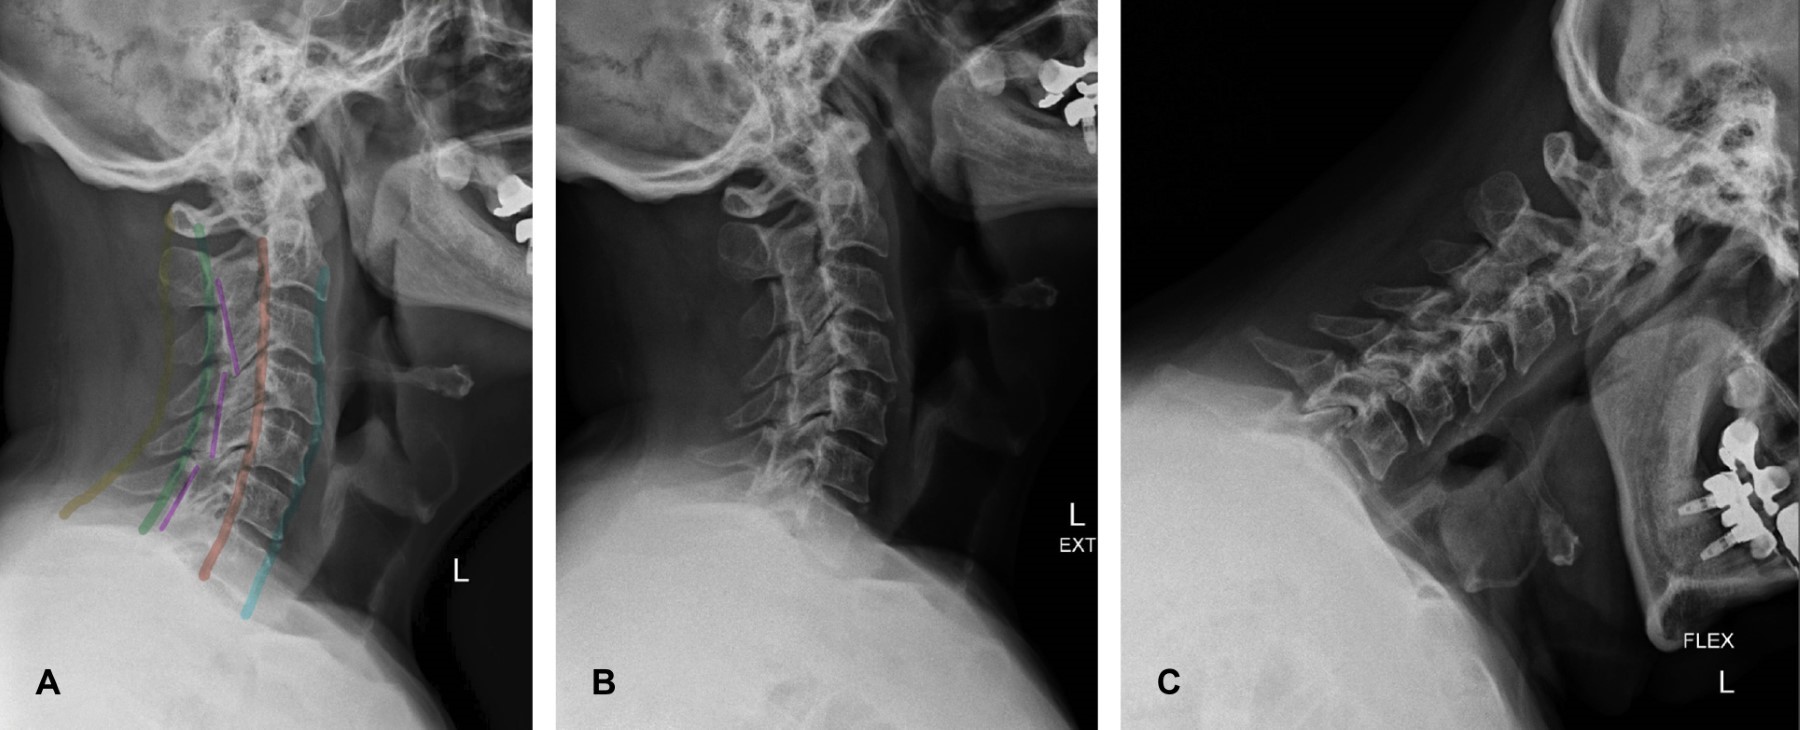

Paciente masculino de 68 años con dolor cervical crónico y limitación a la extensión cervical y actitud antiálgica en hiperflexión, por lo que se solicitan radiografías de columna cervical, se observa esclerosis y subluxación facetarias en C3-C4 y C5-C6 (Figura 1) como hallazgos clave en el diagnóstico de esta patología. La subluxación facetaria es comúnmente ocasionada por una hiperflexión de la columna cervical que afecta con frecuencia a los niveles C5-C6 y C6-C7, en donde la faceta articular inferior del cuerpo vertebral superior se desplaza en sentido posterior de forma parcial o completa a la faceta superior del cuerpo vertebral inferior. Es una de las lesiones de la columna cervical que se pasa por alto con mayor frecuencia en las radiografías simples. Un abordaje sistemático que involucre la definición de las líneas vertebrales, así como una definición de los cuerpos vertebrales, elementos del arco posterior y espacios intervertebrales atribuyen a detectar estas anomalías entre otros hallazgos que pueden distraer al observador y evitar la evolución de este padecimiento a la complicación de una luxación bilateral facetaria, como lesión inestable de la columna.

Figura 1